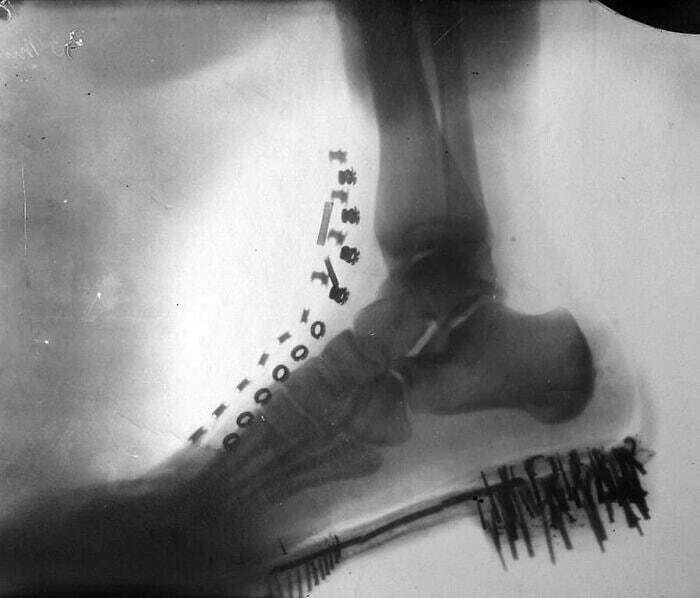

تصویری متفاوت از نیکلا تسلا!

عکس پرتو اکس از پای نیکلا تسلا، مخترع و مهندس مشهور، که توسط خود وی با دستگاهی که طراحی کرده بود در سال 1896 گرفته شده است.

تصویر متفاوت از پای نیکلا تسلا